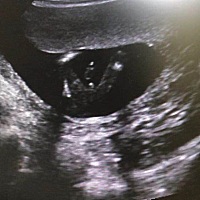

请问下这是有了吗?

孕7周做B超没有胎心胎芽,好苦恼